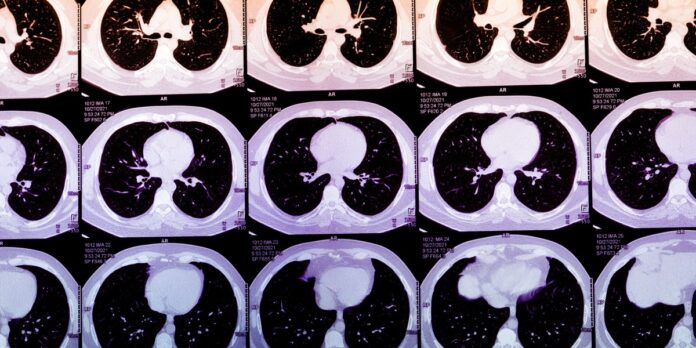

Unlocking Heart Health through AI: The Promise of Coronary Artery Calcium Scores

Coronary Artery Calcium (CAC) testing is an underutilized method for assessing heart attack risk. By highlighting the lifecycle of plaque build-up, CAC testing provides crucial insight into cardiac health. Here’s why it matters:

• Access Expansion: New algorithms can derive CAC scores from routine chest CT scans, enhancing accessibility for patients and doctors.